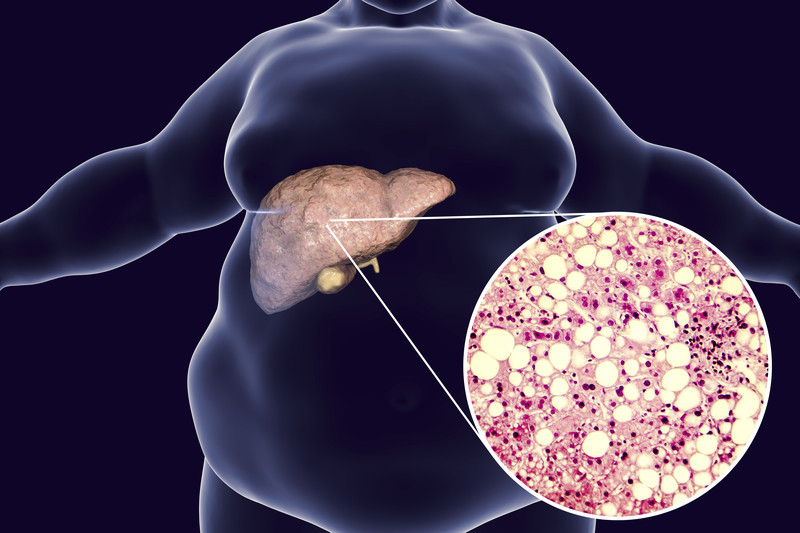

Gordura no Fígado

O acúmulo excessivo de gordura no fígado sem tratamento adequado, pode causar problemas hepáticos graves, incluindo esteato-hepatite não alcoólica (NASH), que causa inflamação e fibrose ou cicatrizes no fígado. E também aumenta o risco de outras condições de saúde, incluindo doenças cardiovasculares

Os primeiros casos documentados de doença hepática gordurosa não alcoólica (DHGNA) só surgiram em 1980. Hoje, a DHGNA afeta 32,4% das pessoas em todo o mundo e é a causa mais comum de transplante de fígado em adultos com menos de 50 anos.